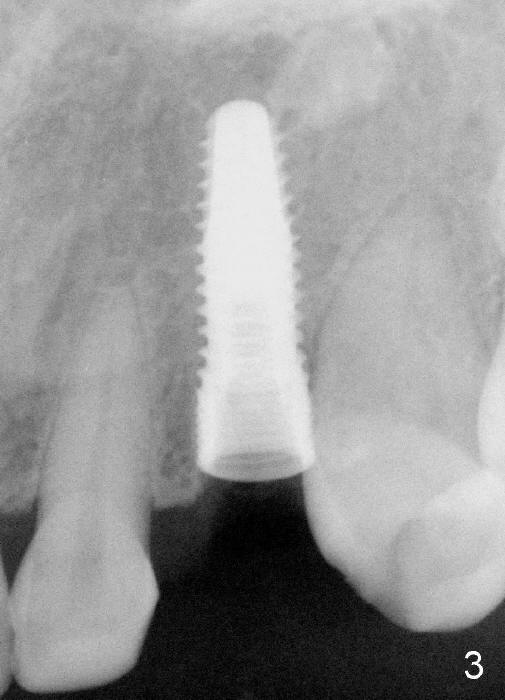

The 42-year-old lady refuses to take antibiotic prior to surgery due to lactation. The extraction of the upper left deciduous canine is not difficult as expected. There appears to be no granulation tissue. What is unexpected is difficulty in osteotomy. Initial osteotomy is too palatal, apparently perforating the palatal plate. The osteotomy has to be changed: slightly palatal to the center of the original socket (Fig.1: 2 mm pilot drill). As drills increase in diameter, the coronal end of the drills have to be tilted buccally, because it feels like that the labial plate at the apical end is going to be perforated. When 4.5x14 mm bone level implant is placed, the implant is sticking out too much (Fig.2). To alleviate this cosmetic issue, the implant is placed deeper (Fig.3). A 25º angled abutment is placed with heavy labial reduction (Fig.4,5). The patient is pleased with a stable new tooth, but the operator is not (Fig.6). Removal of the implant may be not the wildest guess. Two or three days postop, the patient reports pain and swelling. The symptoms disappears after antibiotic. One week follow up reveals wound healing normal. The gingiva returns to its normal color, as compared to purplish appearance in Fig.4,6 (immediately postop). In fact, the implant fails in a month.